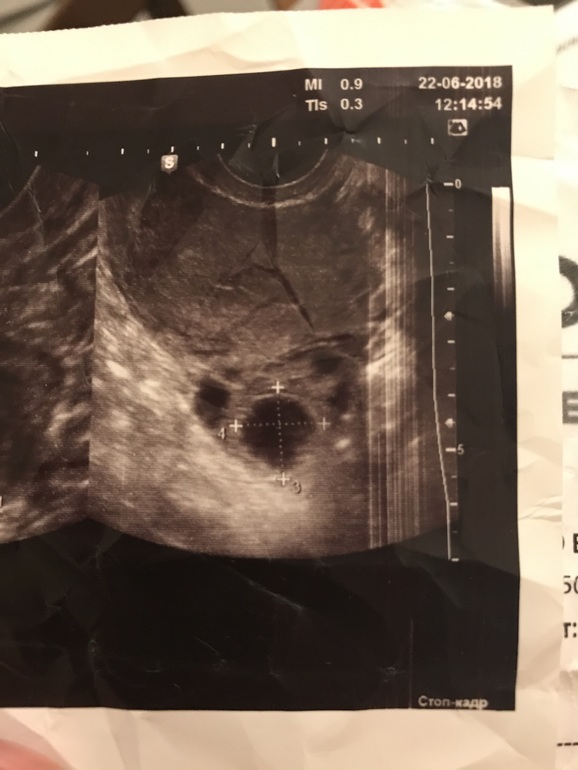

3. УЗИ на 5 дц: доминантных нет(4-6мм), фолликулярная киста 3см

6. УЗИ сегодня (20дц или 8дц, если мазня это М): киста всё там же и так же 3 см,

А вот в ПЯ толи фолликулы 8 и 14 мм, толи фолликул 8 и ЖТ 14 мм

ВОПРОС: что это фолликул или ЖТ?

я не знаю, как врачи работают, если мы уже сами тут узи читать можем. А они каждый день его делают и смотрят. Круглое, черное - фолликул. Непонятное звезчатое со структурой внутри - ЖТ. Что там непонятного?

ЖТ выглядит совсем по другому, так что это ДФ 14мм.

Что ЖТ(регресс)

🤷🏻♀️ Ну тут одно из двух.. либо реально регресс ЖТ - недостаточность второй фазы, поэтому ее и на графике нет, либо все-таки ДФ..

И вот ЖТ.. правда не регресс, а свежее, но оно все равно как-то иначе выглядит)) здесь диаметр его 17мм

оно рябое какое-то

На УЗ-картине желтое тело определяется в виде гиперэхогенного образования, имеющего неоднородное содержимое, находящегося на месте произошедшей овуляции и имеющего размеры 18-30 мм.

У вас классический пример отсутствия ЖТ по УЗИ!

В жт типа такая сеточка должна быть, а полностью чёрное это фолликул